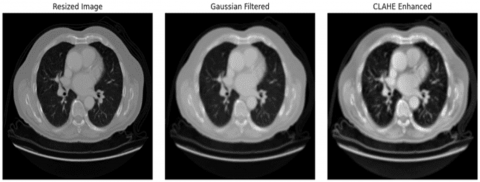

3.2 Image preprocessing

Image preprocessing defines the data preparation phase, where the system converts the raw CT images into an appropriate format for further processing. This stage follows a sequence of processes such as noise filtering, image resizing, and contrast enhancement or background elimination. In the noise filtering step, a Gaussian filter was applied to the images to eliminate the noise or unwanted random variations within each image. The Gaussian filter removes the noise attributes and replaces them with the average value of nearby or surrounding attributes, which is estimated by Gaussian distribution. The mathematical formulation of the Gaussian filter is expressed in Eq. (1):

where, Gs(m, n) represents the Gaussian filter, Cim(m, n) denotes the input CT image, (m, n) indicates the kernel coordinates, and ∂ refers to the standard deviation. Consequently, the filtered images are resized into a common size to boost the dataset consistency. Finally, background removal was done to discard the unwanted regions from the CT images. This process is done using image thresholding. This step helps the system to focus on useful regions in the images. In addition, data augmentation was performed to reduce the risk of overfitting. This step creates new training samples by performing steps like rotation, random translation, scaling, image mixing, etc. Figure 3 displays the preprocessed images.

Figure 3. Preprocessed images